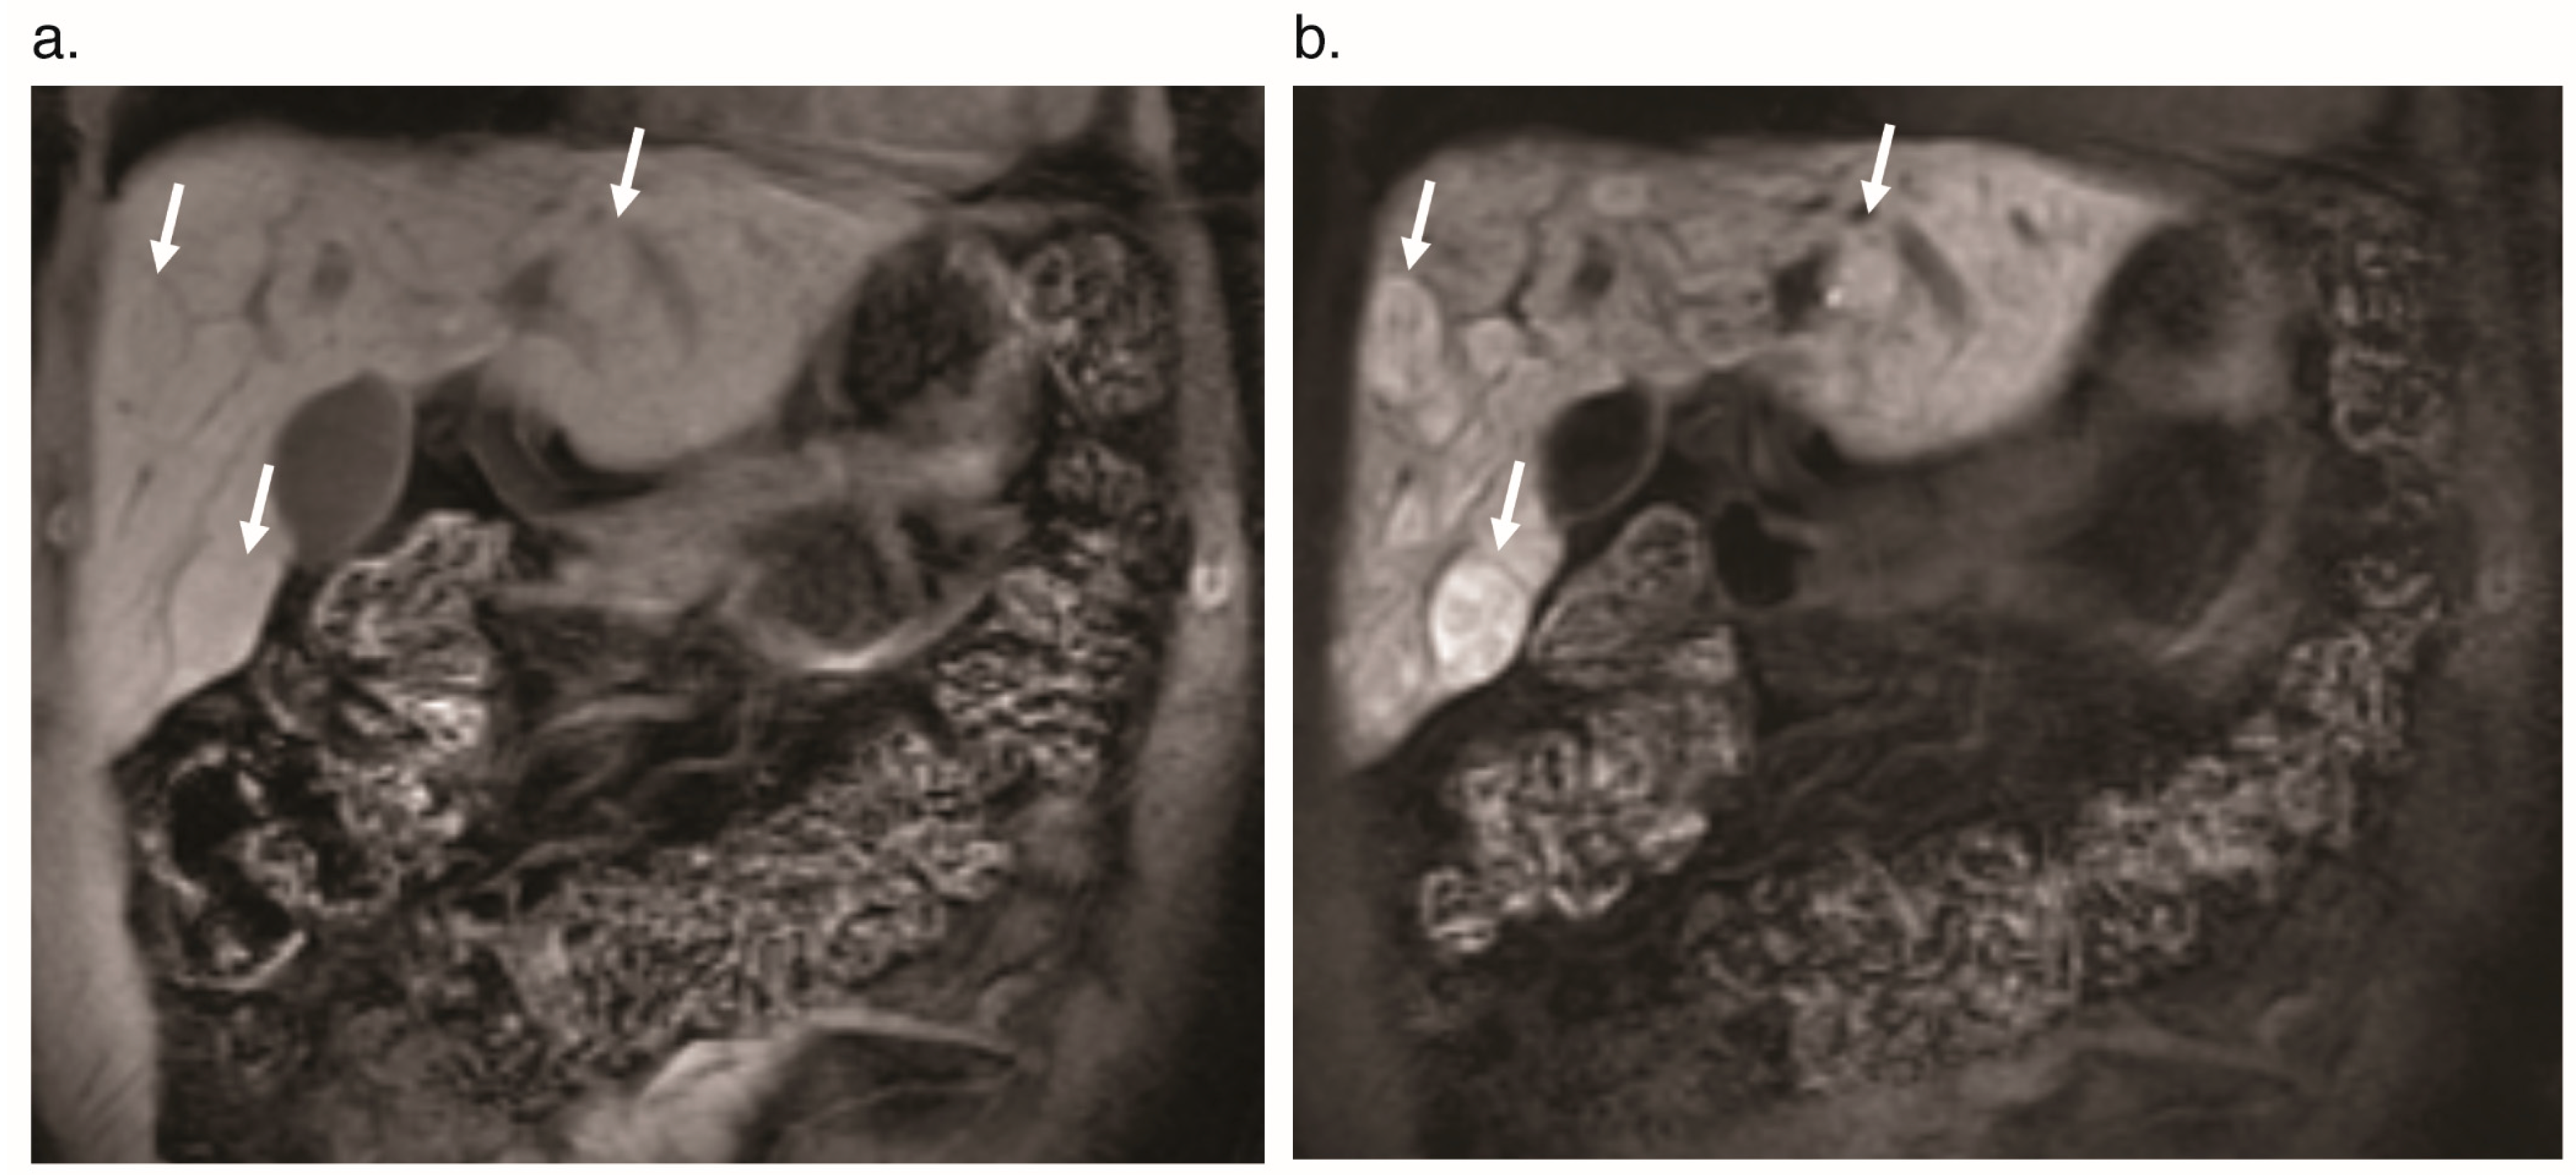

6.2. Focal Nodular Hyperplasia

- Buscarini, E.; Danesino, C.; Plauchu, H.; De Fazio, C.; Olivieri, C.; Brambilla, G.; Menozzi, F.; Reduzzi, L.; Blotta, P.; Gazzaniga, P.; et al. High prevalence of hepatic focal nodular hyperplasia in subjects with hereditary hemorrhagic telangiectasia. Ultrasound Med. Biol. 2004, 30, 1089–1097. [Google Scholar] [CrossRef]

- Scardapane, A.; Ficco, M.; Sabba, C.; Lorusso, F.; Moschetta, M.; Maggialetti, N.; Suppressa, P.; Angelelli, G.; Ianora, A.A.S. Hepatic nodular regenerative lesions in patients with hereditary haemorrhagic telangiectasia: Computed tomography and magnetic resonance findings. La Radiol. Med. 2012, 118, 1–13. [Google Scholar] [CrossRef]